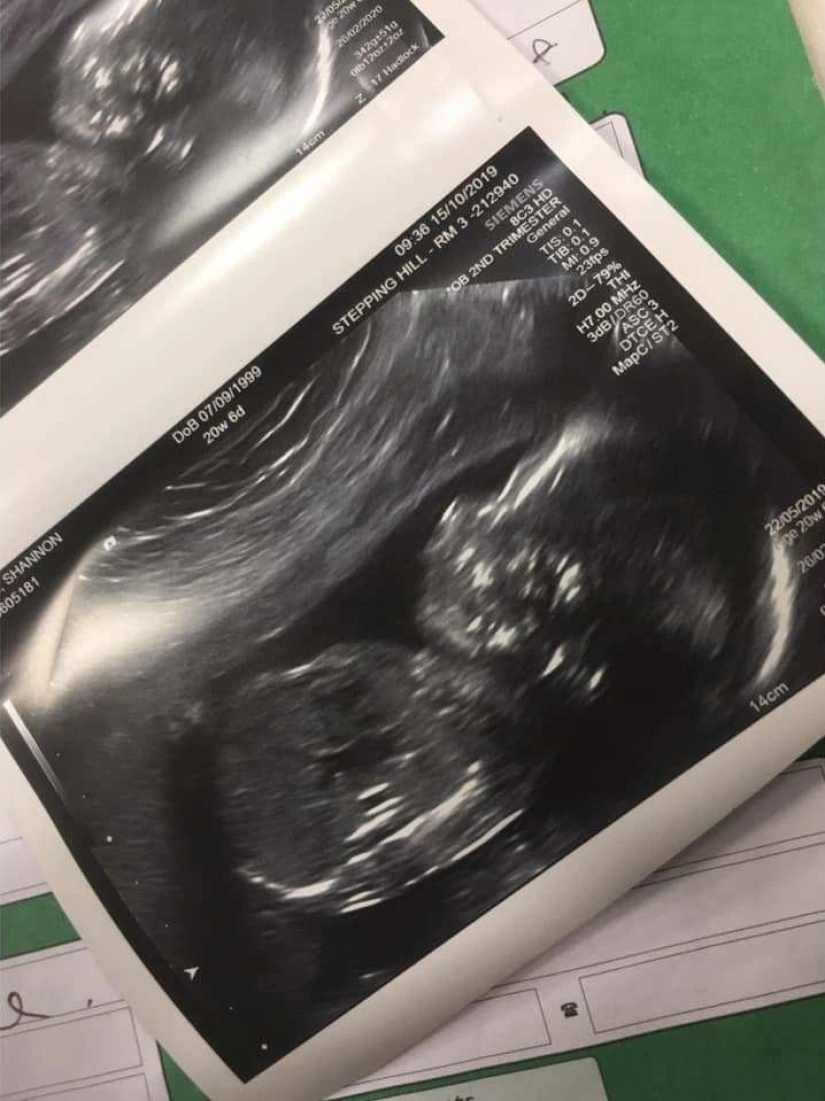

Lesbianas encontró candidato para el papel del padre biológico de su bebé en abril de 2019. Dos meses más tarde, Shannon se quedó embarazada mediante inseminación artificial, utilizando el conjunto, comprado en Amazon.

13 de febrero de este año, Shannon dio a luz a una niña sana océano Mabel de la rosa. Su pareja Katie ya tiene 2 años de edad, hija, que ella también tenía un bebé con un donante de esperma.

Desde Shannon había terrible enfermedad de la mañana hasta las 25 semanas de embarazo, pero ella estaba dispuesta a soportar todo por el bien de convertirse en madre. El bebé nació a las 38 semanas por parto vaginal.